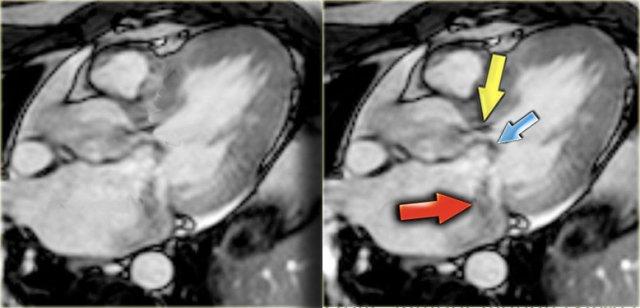

HCM với đường ra thất trái hẹp (mũi tên vàng), chuyển động ra trước tâm thu của lá van trước van hai lá (mũi tên xanh dương) và hở van hai lá (mũi tên đỏ)

Trên hình ảnh cuối tâm thu, có thể thấy các dấu hiệu sau (hình):

- Dòng phụt trong đường ra thất trái bị hẹp

- Chuyển động ra trước tâm thu của lá van trước van hai lá

- Hở van hai lá